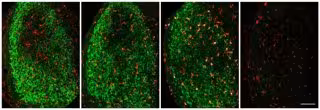

NORRIS ET AL., 2018

El científico Jonathan Kipnis, presidente del Departamento de Neurociencia de UVA, y sus colegas examinaron las lesiones del nervio óptico de los ratones, que hacen que las neuronas ganglionares de la retina se degeneren y dejen residuos en una región distante del cerebro. Los investigadores encontraron que esta suciedad es absorbida por la microglía.

En los cerebros de adultos, la microglía parece reconocer las neuronas degenerativas usando algunas de las mismas moléculas que usan para reconocer las sinapsis inactivas o los patógenos invasores. Kipnis y sus colegas encontraron que, después de la lesión del nervio óptico, la microglía produce proteínas "complementarias" que ayudan a las células fagocíticas a identificar sus objetivos.

Los científicos estudiaron lo que sucedió después de la lesión del nervio óptico en ratones cuando la microglía no produjo proteínas del "complemento" y descubrieron que la microglía no eliminaba los restos. "En el futuro, esperamos identificar aún más cómo se activan las microglías en respuesta a la neurodegeneración y cómo luego eliminan los desechos neuronales --dice Kipnis, director del Centro de Inmunología Cerebral y Glia de UVA--. Conocer estos mecanismos podría permitirnos aumentar la eliminación de restos potencialmente tóxicos por la microglía y limitar la propagación de la neurodegeneración tras una lesión en el cerebro o la médula espinal".